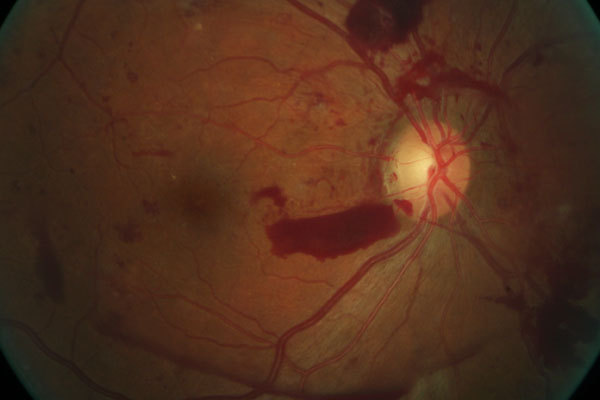

Retinal photos can assist in early detection of retinal problems like retinal detachment, holes or thinning, optic nerve disease, pre-cancerous lesions,

macular degeneration, hypertensive retinopathy, diabetic retinopathy, glaucoma changes and others.